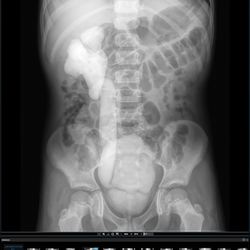

Colon 1

Pielo

SEGD

Urografía